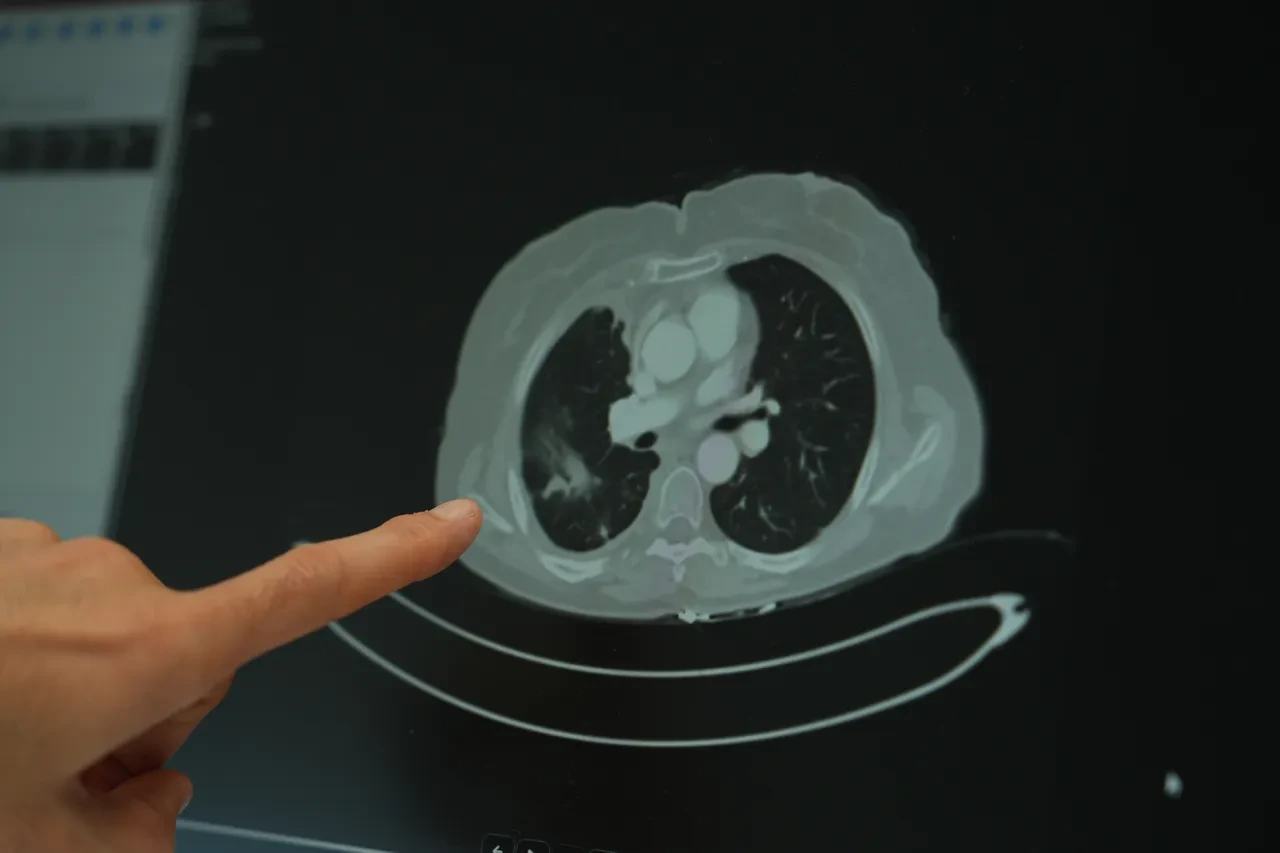

Ailesinde kanser öyküsü bulunan gençlerin çok daha dikkatli olması gerektiğini vurgulayan Doç. Dr. Şimşek, “Ailede kanser varsa, tarama yaşları çok daha genç yaşlara çekilebiliyor. Bazı durumlarda 18-20 yaşlarından itibaren düzenli kontrollerin yapılması hayati önem taşıyor” diye konuştu. Sigara kullanımının akciğer kanseri üzerindeki etkisini değerlendiren Doç. Dr. Şimşek, uzun süre sigara kullanan kişilerde düşük doz radyasyonla yapılan tomografi taramalarının önerildiğini belirtti. “Sigara içen bireylerde akciğer kanseri riski yüksek. Bu nedenle düşük doz radyasyonlu taramalar, erken tanı açısından önemli” ifadelerini kullandı.